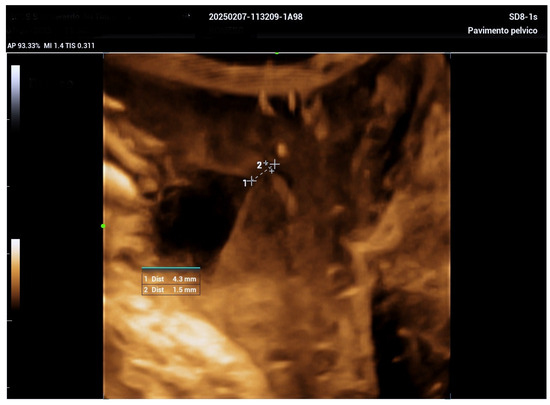

Managing Urethral Diverticulum During Pregnancy Utilizing Advanced Ultrasonographic Techniques: A Literature Review and Case Study

2. Case Report

| Jeong et al. [5] | Suprapubic pain, purulent discharge, leakage | 5.5 cm | TVUS, TPUS, 3D ultrasound at 34 weeks | Antibiotics; aspiration considered | Planned vaginal delivery | Postpartum diverticulectomy |